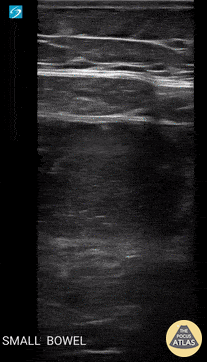

30-year-old presented with 2-day history of abdominal pain, abdominal distention, and vomiting. Pertinent PMH includes prior hemicolectomy due to Crohn's disease. Seen here is POCUS evidence of SBO. Ahmad Khan @kadiwls